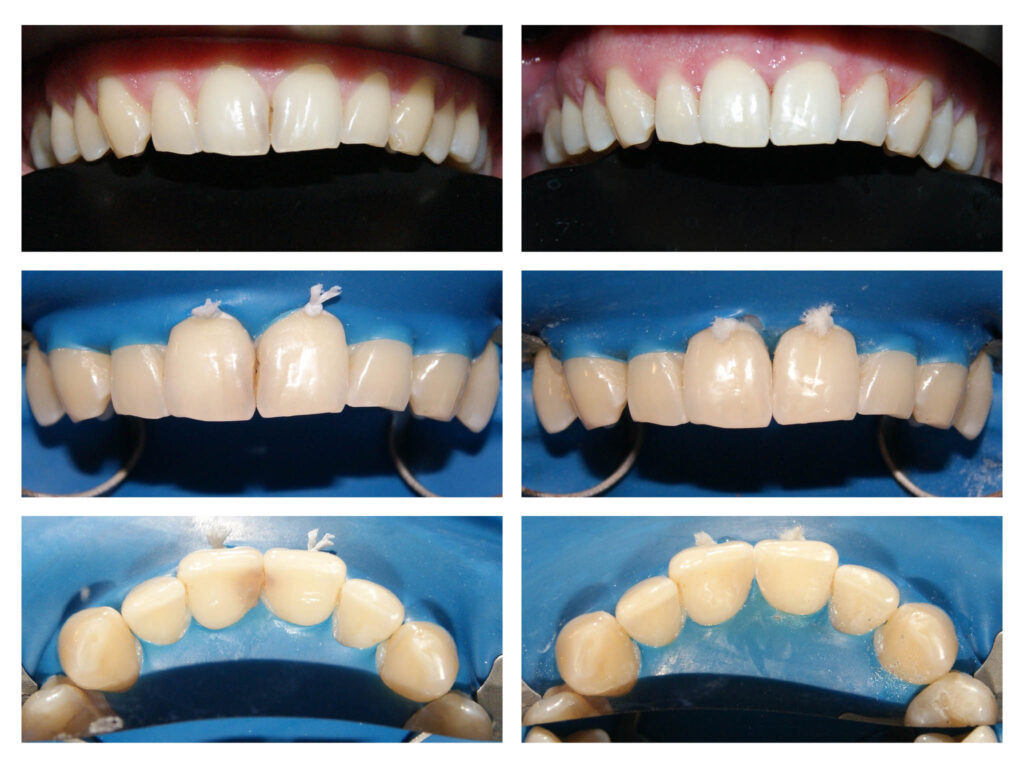

Lucrare protetică din Zirconiu stratificat- integrare estetică- praguri minim invazive pe dinți tineri, vitali – gingii sănătoase

Lucrări protetice din zirconiu cu adaptare perfectă